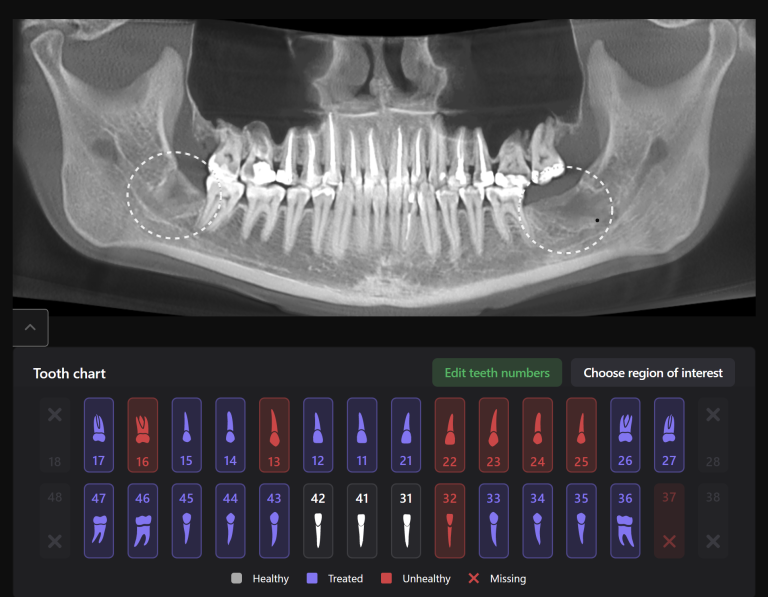

Solution: Diagnocat’s reports, based on CBCT and intraoral scans (STL files), help the clinician to quickly and accurately make decisions about treatment tactics and final tooth position, and to plan comprehensive treatment according to the individual needs of the patient